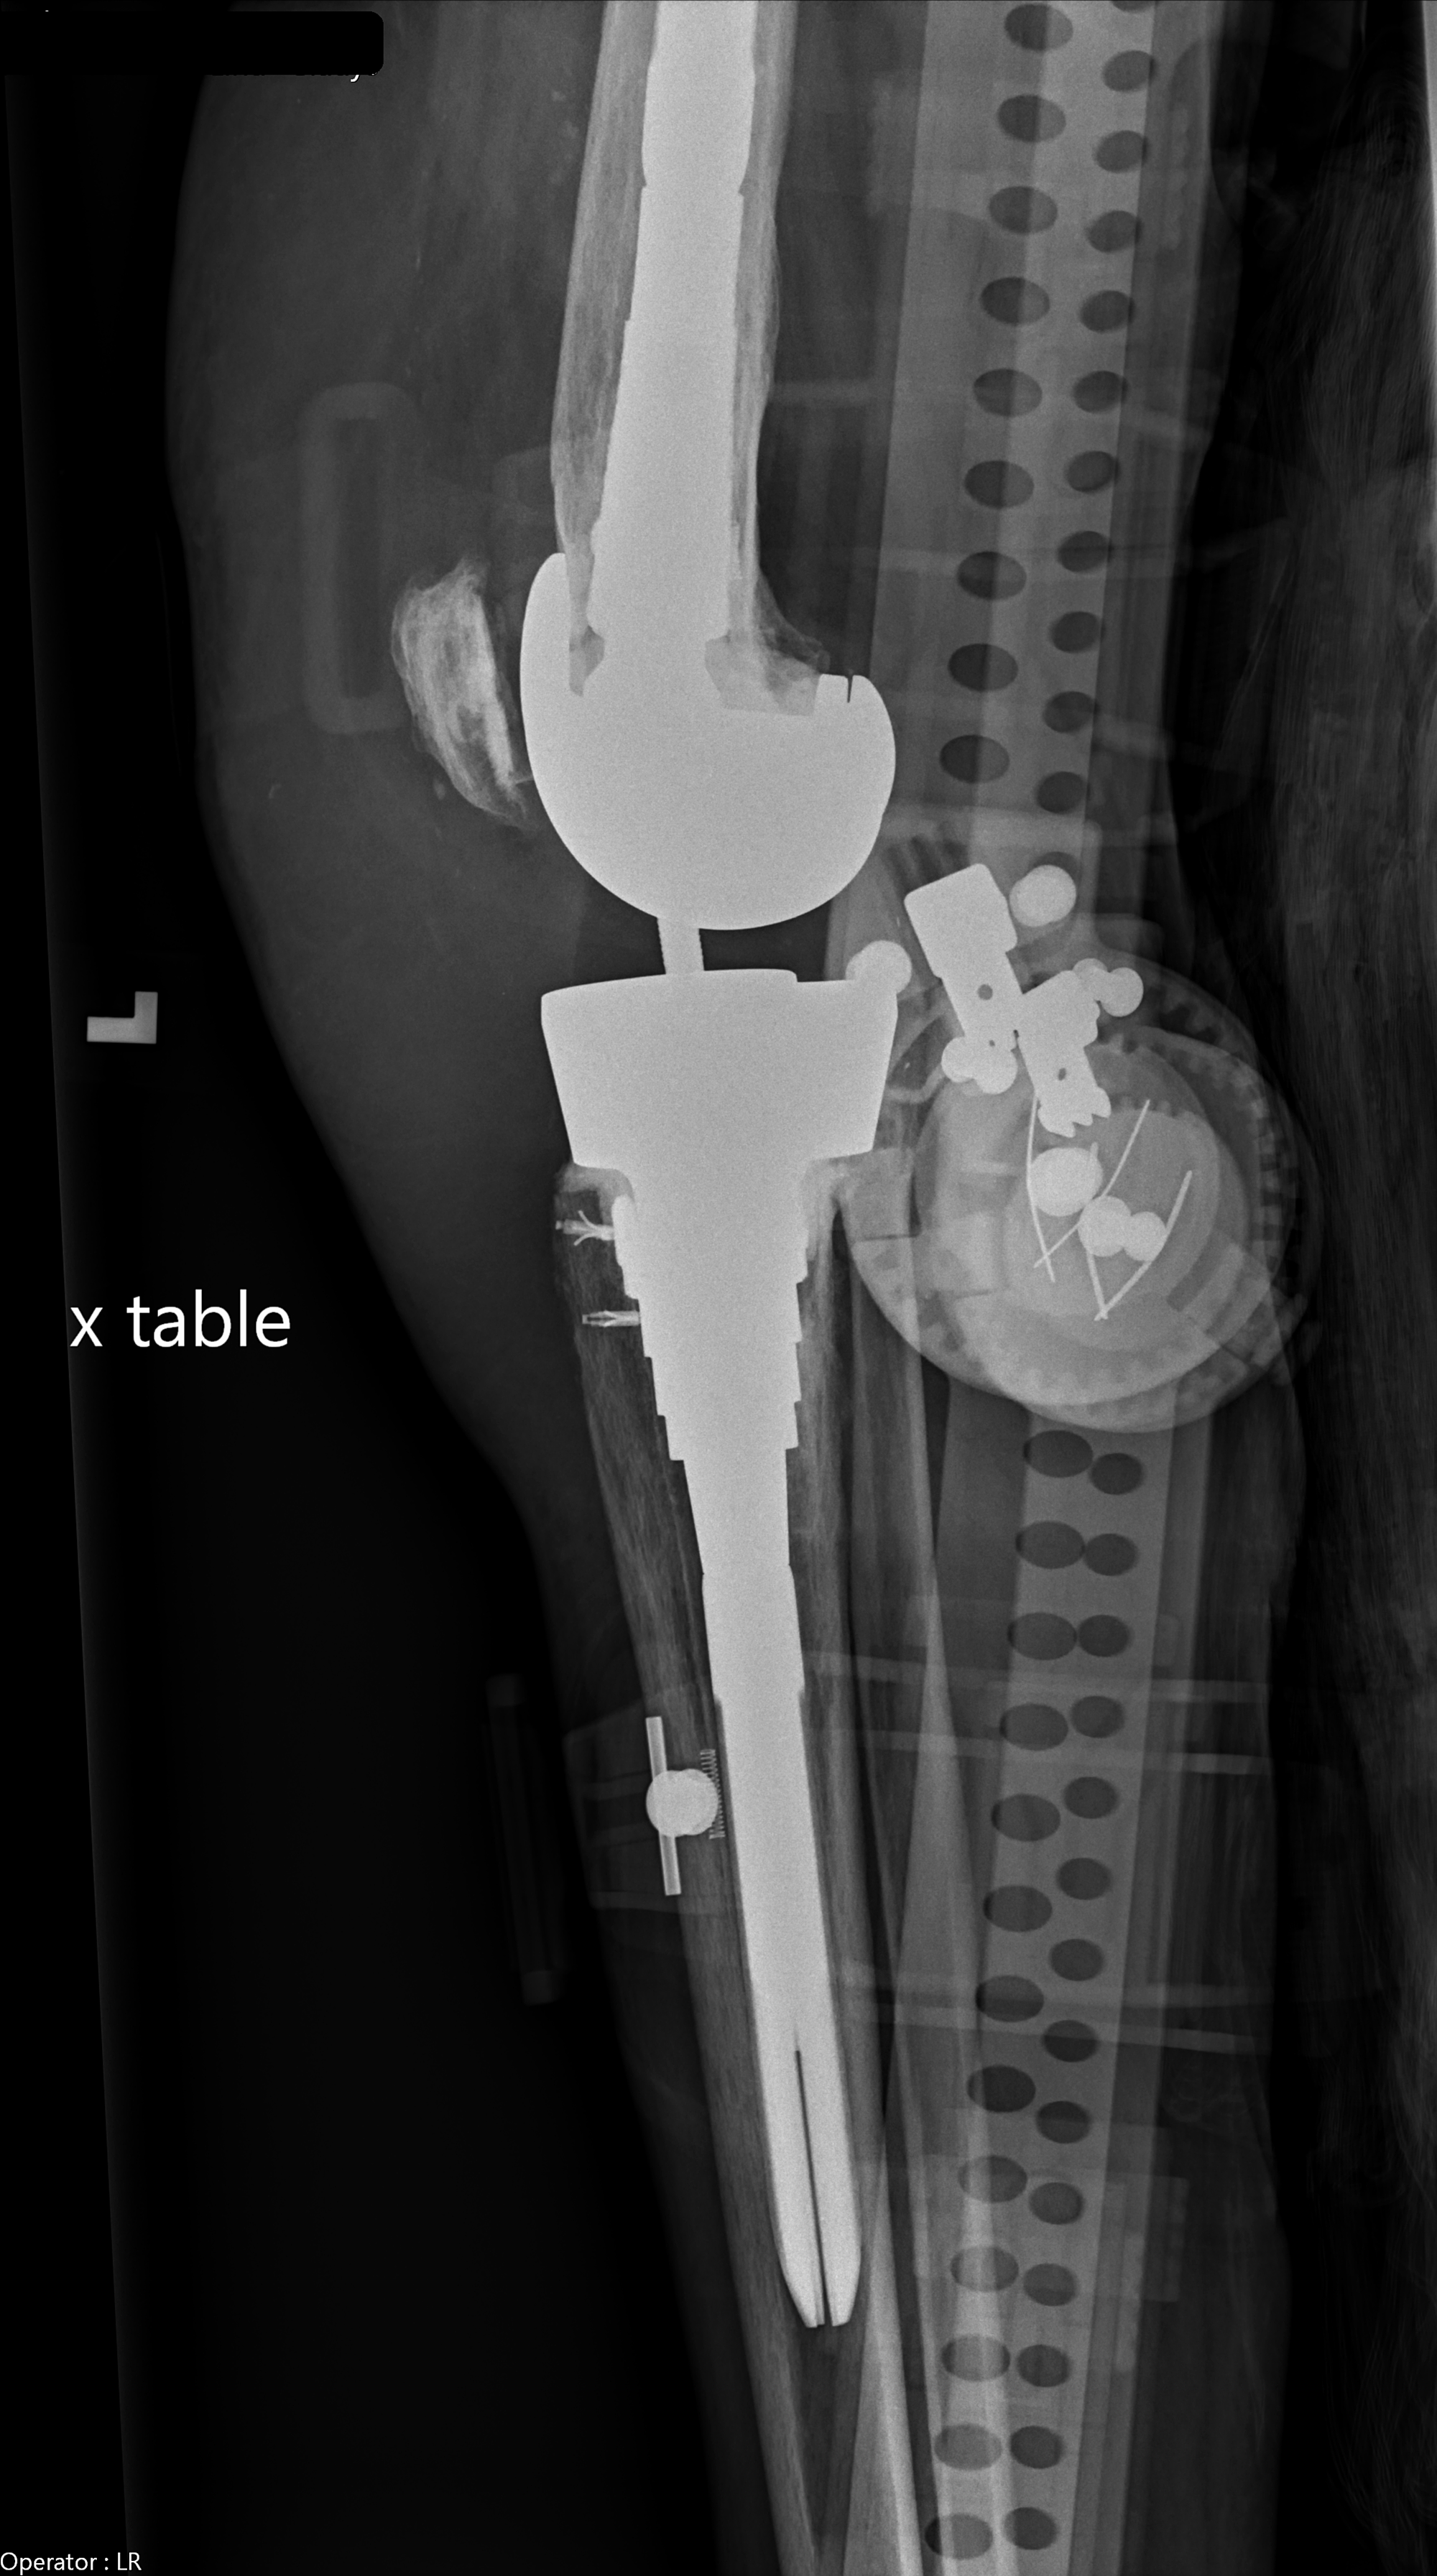

Cureus Rare Occurrence of Prosthetic Knee Septic Arthritis Due to Strep Infection Knee Replacement The duration of antibiotic therapy in patients with prosthetic joint infection is primarily based on expert recommendations rather than evidence. 47 had infections of total hip arthroplasty and 23 had infections of total knee arthroplasty. Seventy patients with monomicrobial infections were included: Symptoms can include increased pain and stiffness, an inability to walk,. 3,4 patients usually receive long courses of.. Strep Infection Knee Replacement.

Causes of infection associated with prosthetic joints. There are two Strep Infection Knee Replacement Symptoms can include increased pain and stiffness, an inability to walk,. 3,4 patients usually receive long courses of. The duration of antibiotic therapy in patients with prosthetic joint infection is primarily based on expert recommendations rather than evidence. Seventy patients with monomicrobial infections were included: 47 had infections of total hip arthroplasty and 23 had infections of total knee arthroplasty.. Strep Infection Knee Replacement.

Group B Streptococcal Prosthetic Knee Joint Infection Linked to the Strep Infection Knee Replacement A small number of patients undergoing hip or knee replacement (about 1 in 100, or 1%) may develop an infection after the operation. Joint replacement infections may occur in the wound or deep. The duration of antibiotic therapy in patients with prosthetic joint infection is primarily based on expert recommendations rather than evidence. Seventy patients with monomicrobial infections were included:. Strep Infection Knee Replacement.